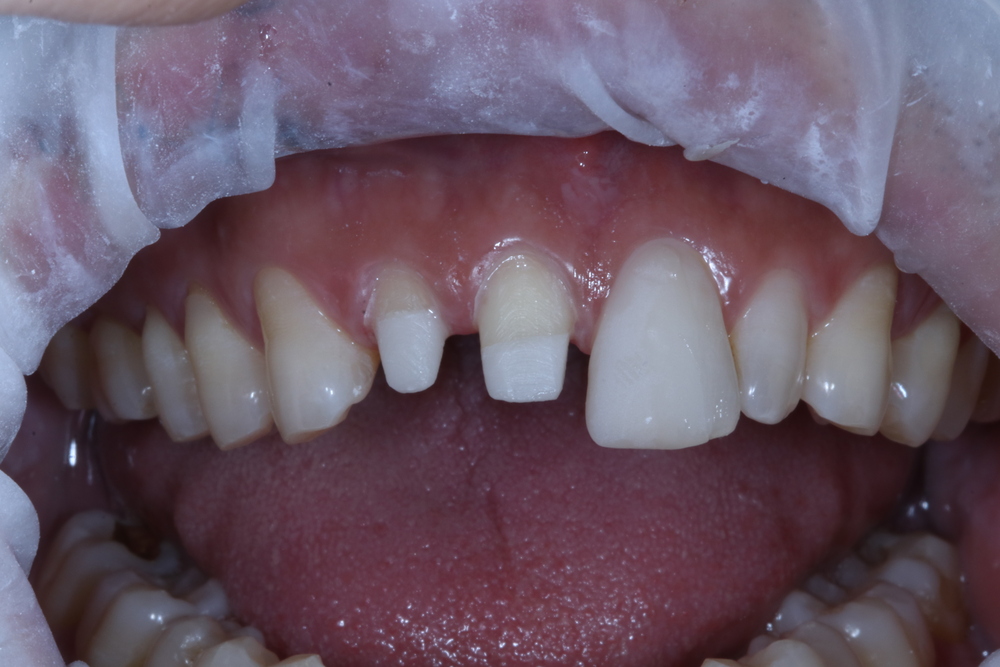

지르코니아 기둥을 바로 만들어 끼운 모습이에요. 앞니에서 보면 치아가 많이 남은 것 같아요. 하지만...

사실 안쪽이 너무 깊은 부위까지 없어져서 좀 불안은 했습니다. 신경치료와 기둥 모두 당일에 다 치료를 진행했어요. 디지털방식 기공이라 촬영 후 제가 직접 모두 만들었어요.

치아모양을 디자인해 보니 동생의 앞니가 원래 살짝 벌어져 있었던 가봐요. 그냥 하려니 부러진 대문니가 너무 커지는 상황이라 바로 옆 대문니에 삭제없이 세라믹을 부착해서 크기를 맞추어 주었어요. 그리고 그 옆의 치아는 반대편 측절치가 짧고 작은 편이라 너무 크지 않게 만들어 주었구요.